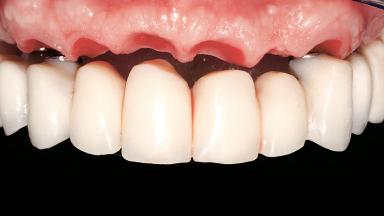

Immediate Loading of Six Implants in the Maxilla and Final Restoration with a Full-Arch CAD/CAM Zirconia FDP

A 63-year-old male patient was referred for a consultation and treatment of partial edentulism in the maxilla. The patient presented with residual anterior teeth and declined a partial removable prosthesis. He reported that the maxillary posterior teeth had been extracted due to mobility and periodontal disease two months before the consultation. The patient’s chief complaint was that his residual maxillary teeth were mobile and that he was unable to chew. The patient’s desire was a stable and comfortable fixed maxillary rehabilitation. The patient was a light smoker (fewer than 10 cigarettes/ day), and his medical history was without significant findings. He was not on any regular medication at the time of consultation. The extraoral examination revealed a normal physiognomy with a correct distribution of the facial thirds. The patient presented a low lip line, and the transition line between teeth and soft tissues was not exposed during a forced smile.

Abutment Type CAD/CAM

Prosthesis Type FDP